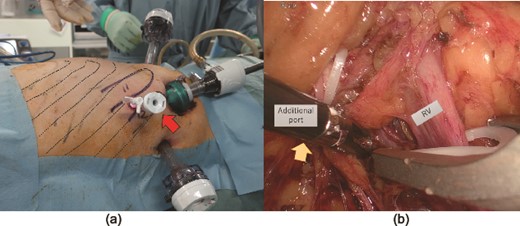

The patient was placed in the left lateral decubitus position. The retroperitoneal space was created using a PDB balloon dissector (Covidien Ltd., Mansfield, MA, USA). The ports were placed as shown in Fig. 2a. Although the renal vessels could be exposed, vascular control is difficult. Forceps could not reach the suprahilar area via the lateral port because the iliac crest interfered with forceps movement (Fig. 2b). Therefore, according to the preoperative plan, a 5 mm port was added at the intercostal site, as indicated in Fig. 3a. The trocar accessed the retroperitoneal space directly without injuring the pleura or diaphragm. The additional port secured the manual placement of the suprahilar area and ensured safe vascular control. The port also secured the handling of the superior aspect of the kidney and the successful completion of laparoscopic surgery (Fig. 3b). The lower ureter and bladder cuff were dissected, and en bloc specimens were retrieved via a Gibson incision.

(a) A 5 mm port added at the intercostal site (arrow). Dotted lines indicate the ribs. (b) The additional intercostal port secured access to the supra hilar area (arrow), allowing for safe renal vascular control and manipulation of the superior aspect of the kidney. RV: renal vein.